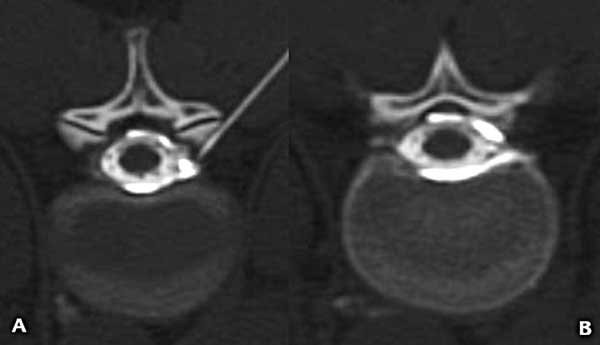

Luego de analizar las imágenes se decidió abordar el quiste radicular. En decúbito ventral se dirigió una aguja espinal 21G hasta el neuroforamen, inyectando 2 cm3 de lidocaína al 1% marcada con contraste yodado, se identificó, así, el llenado del componente extradural del quiste sin pasaje al saco tecal (Figura 4); comprobado esto, se inyectaron seguidamente 10 cm3 de sangre autóloga recientemente extraída a la paciente.

Figura 4. Mielo-TC. A) Corte axial donde se puede ver el extremo de la aguja en el neuroforamen y el medio de contraste que rellena el espacio peridural. B) Corte axial inmediatamente por encima de la figura 3 en el que se observa el medio de contraste concentrado en el espacio peridural sin pasaje al interior del saco tecal.